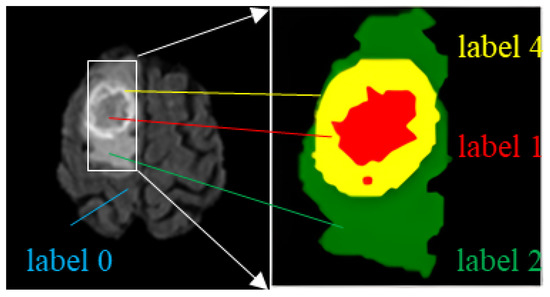

There are four label categories in the dataset: label 0 represents a healthy region; label 1 represents a region of necrotic and non-enhanced tumors; label 2 represents a peritumor edema region; and label 4 represents an enhanced tumor region. Brain tumors need to be segmented into three regions: the WT region, the TC region, and the ET region. WT includes the regions with labels 1, 2, and 4; TC includes labels 1 and 4; ET includes only label 4, as shown in Table 2. An example of an MRI brain tumor image is shown in Figure 5, where each label is represented using a corresponding color: label 1 region with red, label 2 with green, and label 4 with yellow.

Figure 5. Different labels and tumor regions in MR images.